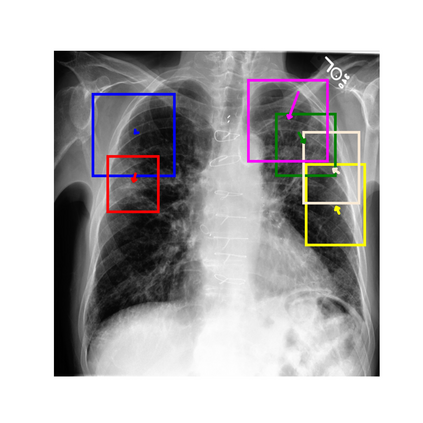

To address these issues, we propose a novel Adaptive patch-word Matching (AdaMatch) model to correlate chest X-ray (CXR) image regions with words in medical reports and apply it to CXR-report generation to provide explainability for the generation process. AdaMatch exploits the fine-grained relation between adaptive patches and words to provide explanations of specific image regions with corresponding words. To capture the abnormal regions of varying sizes and positions, we introduce the Adaptive Patch extraction (AdaPatch) module to acquire the adaptive patches for these regions adaptively. In order to provide explicit explainability for CXR-report generation task, we propose an AdaMatch-based bidirectional large language model for Cyclic CXR-report generation (AdaMatch-Cyclic). It employs the AdaMatch to obtain the keywords for CXR images and `keypatches' for medical reports as hints to guide CXR-report generation. Extensive experiments on two publicly available CXR datasets prove the effectiveness of our method and its superior performance to existing methods.